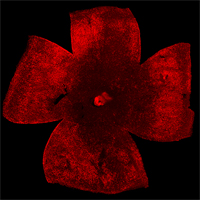

| Retinal Flat mount showing surviving cones in red at 2 months of age. Right image shows effect of loss of mTORC1 (fewer surviving cones at 2 months of age). Role over image to see the effect of increased mTORC1 activity on cone survival at 2 months of age. | |

To evaluate the long-term therapeutic potential of the insulin/mTOR pathway on cone survival, and test if insulin acted directly on cones through this pathway, we have now constitutively activated this pathway in cones through use of mouse genetics in two mouse models of Retinitis Pigmentosa. This has led to a robust and unprecedented cone survival effect in two mouse models of Retinitis Pigmentosa and to the finding that cone survival is driven solely by increased mTOR complex 1 activity (rollover image; Venkatesh et al., 2015). To study why the initial robust survival effect of constitutively activated mTORC1 does not persist indefinitely we further study the consequences of altered mTORC1 activity (Venkatesh et. al., 2016). Our studies show that it is not the strength of survival is directly dependent of the strength of mTORC1 activation but that the duration of the effect depends on the system's ability to intermittently turn of mTORC1. This knowledge will allow us to identify downstream genes of mTORC1 that mimic the positive effect of increased mTORC1 activity, without altering the systems ability to intermittently turn of mTORC1. In summary, the knowledge gained from these two studies will allow us to identify downstream target genes or pathways that when manipulated should extend vision in affected individual (see Jean Bennett commenting). For example, rAAV mediated gene transfer of mTORC1 targets in cones may provide a feasible approach for future treatments in humans. Alternatively, drugs that increase mTORC1 activity could be delivered to the retina through slow releasing eye implants. The focus of our current research is to identify the correct mTORC1 targets that can be used to prolong vision in humans with Retinitis Pigmentosa.